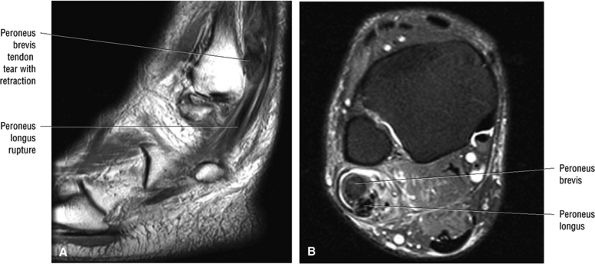

|